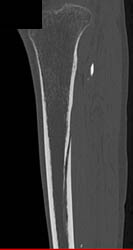

Cellulitis